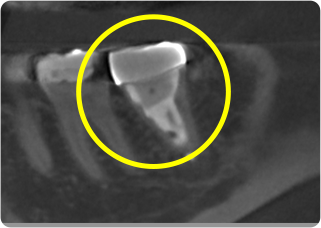

精密根管治療③

術前

術後

| 主訴 | 奥歯で噛むと痛い |

|---|---|

| 治療期間/回数 | 1ヵ月、4回 |

| 価格(税込) | 88,000円(税込) |

| リスク・副作用 | 病変再発、歯根破折の可能性 |

| ポイント | う蝕検知液を用い、むし歯の取り残しが無いようにし、ラバーダム防湿を行い、無菌的に根管治療を行った。根管充填材は、殺菌作用の強い保険適応外のMTAセメントを使用した。 |